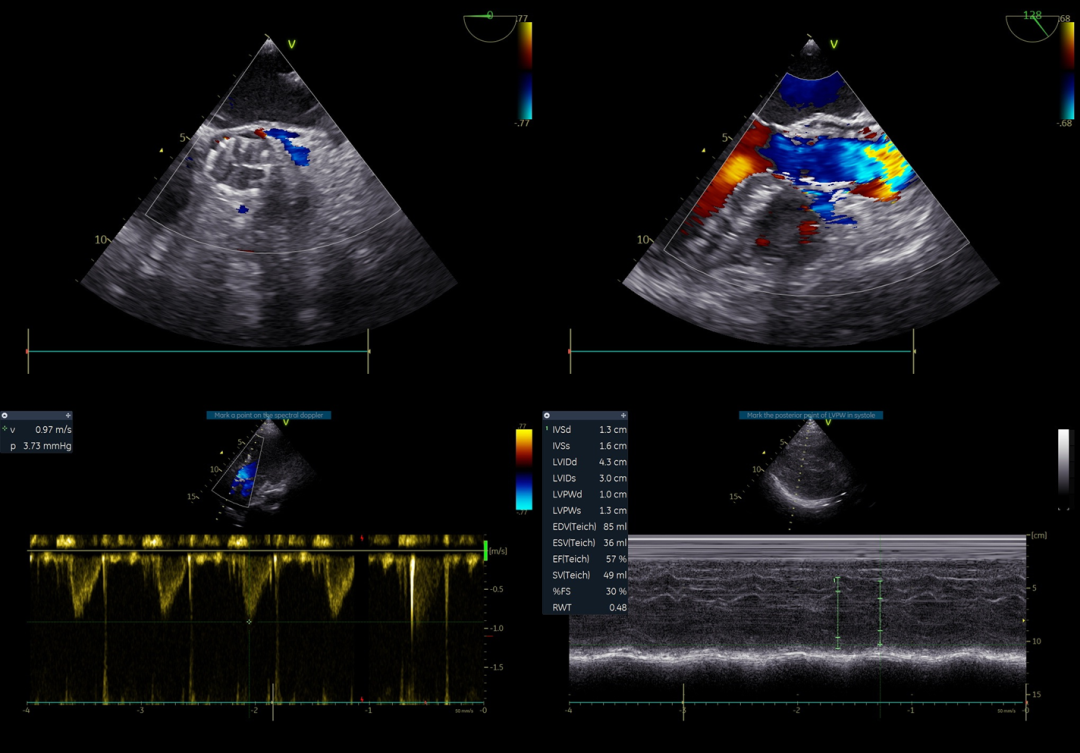

术前超声诊断:瓣口最大流速Vmax = 4.17m/s ,平均跨瓣压差69 mmHg ,EF值 56%。伴有主动脉瓣、二尖瓣中量反流。

超声评估:

超声评估血流动力学改善明显

跨瓣压差: